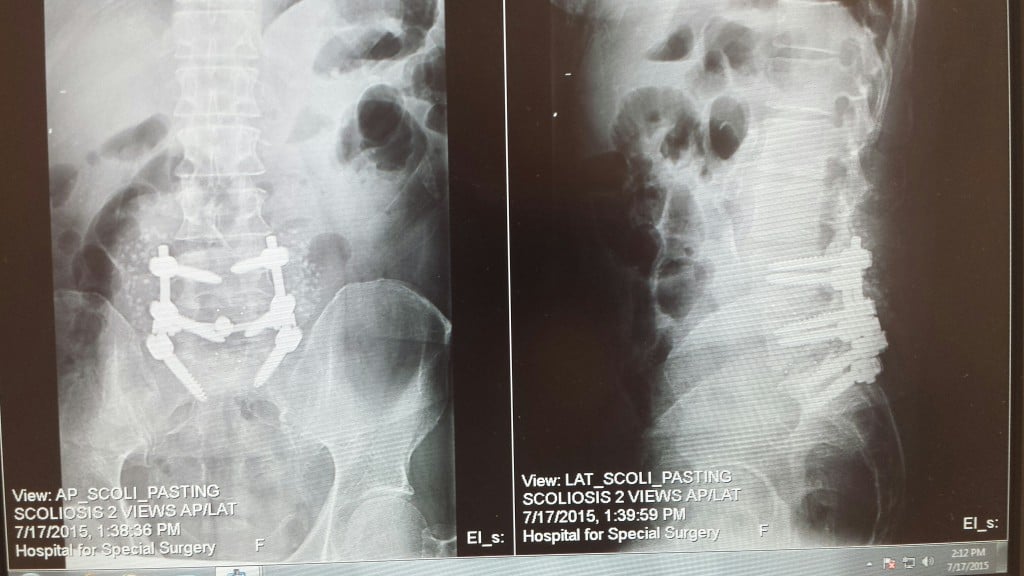

In September of 2015 I began having back and leg pain on my right side. As the pain got worse, I tried a chiropractor, then physical therapy. The pain kept getting worse so thinking that I had a hip problem, I made an appointment with my orthopedic surgeon at HSS. After x-rays and examination, Dr. Nestor determined that the problem was not my hip, but with my lower back and he referred me to a physiatrist, Dr. Wyss, also at HSS. We tried two epidural injections with no improvement. Although scheduling me for a third epidural, Dr. Wyss had the foresight to suggest that I consult with a back surgeon and recommended Dr. Cunningham.

The surgery went smoothly and the care that I received from HSS was amazing. Everybody from the surgeon, the nurses, the physical therapists to the people who changed the bed and generally cared for me was wonderful. Pleasant, helpful, caring and professional.

Currently, almost two months after my surgery I am walking around on my own almost pain free and feeling wonderful. I am particularly thankful to Dr. Cunningham who did such a great job with my surgery, to his PA Brenda, who always answered all my questions and returned my phone calls promptly, and to Tina for coming to my aid in my time of need.